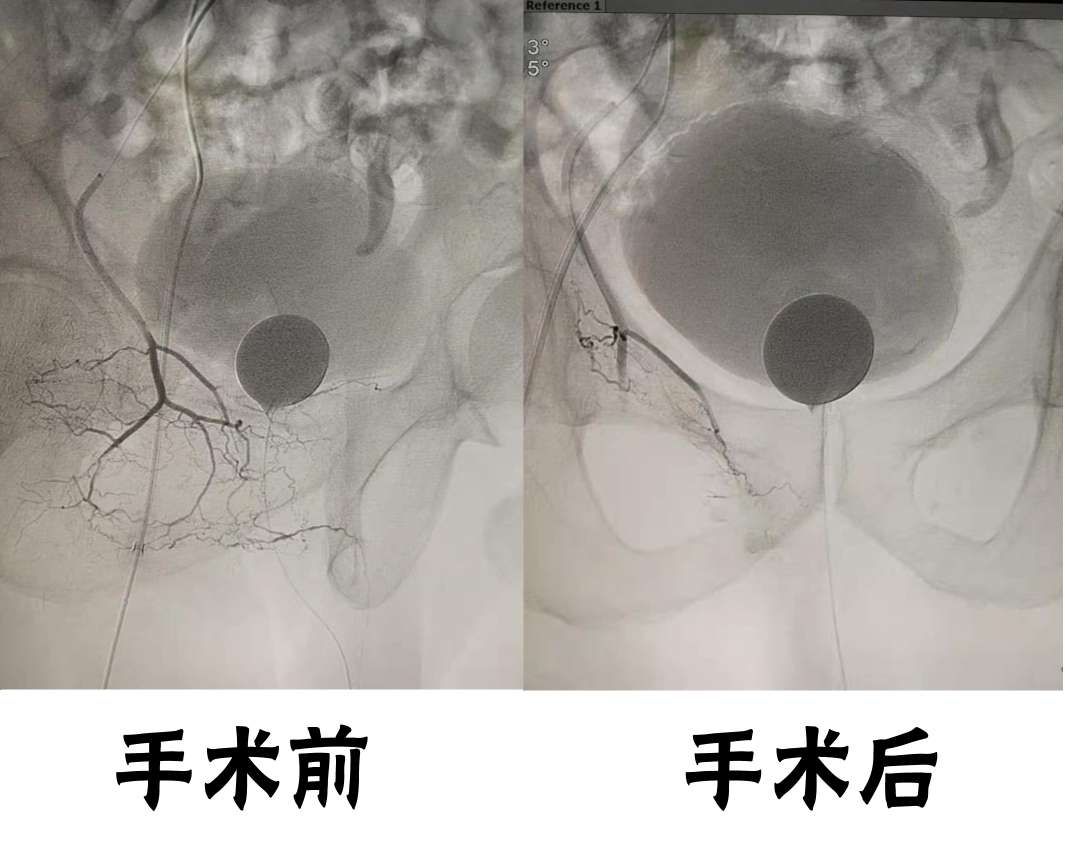

8月27日,桓台县人民医院介入血管外科成功为一例老年前列腺增生肥大患者实施前列腺动脉栓塞术,此项手术在桓台县尚属首例,标志着我院介入技术在前列腺增生治疗领域取得了新突破。

患者为80多岁男性,因前列腺增生肥大无法正常排尿,患者心肺功能差,无法承担麻醉及开刀手术的风险,经药物保守治疗,治疗效果不明显,每次小便都需30分钟以上,且尿频尿不尽,严重影响生活质量。 8月27日,介入血管外科为这位高龄患者行前列腺动脉栓塞术,术后患者感觉良好,无疼痛不适,解决了这位高龄患者的难言之隐。 前列腺增生是中老年男性比较常见的泌尿系统疾病,临床症状表现为;尿频、尿不尽、排尿困难、夜尿增多等,且因为身体有异味,常被人嫌弃,给患者身体和精神带来极大痛苦。 介入血管外科王立军主任介绍,前列腺动脉栓塞可以为患者切切实实地解除困难,其优点是降低了常规手术带来的风险,术后恢复快。它是一种创伤小、疗效明显、安全性强、并发症少的新方法,有效地减少了住院时间、降低了治疗费用,尤其适用于年老体弱、合并心肺并发症、无法耐受麻醉、手术风险和拒绝接受外科手术的治疗者。 目前我院介入血管外科能够独立熟练的开展此项技术,为广大前列腺增生患者开辟了新的治疗途径。

传统治疗前列腺肥大手术是经尿道前列腺电切,把阻塞后尿道的肥大前列腺切除或部分切除,达到治疗的目的,但手术需要全麻或腰麻。而国内外前沿的前列腺动脉介入栓塞术是在不开刀的基础上,局麻将前列腺供血动脉栓塞,使前列腺供血量减少,以达到前列腺腺体萎缩,体积缩小,解除压迫,恢复尿道通畅,改善临床症状的目的。该技术的另一大优势是能够最大限度的保护患者的男性生理功能。